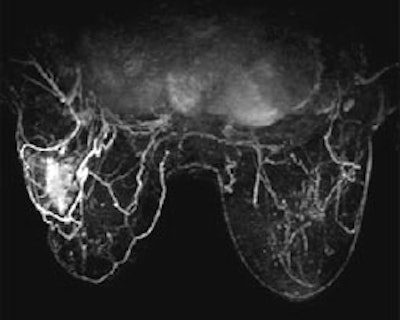

Because of the large amount of data and clinical images produced from breast MRI studies, a truly integrated and effective CAD system is a critical tool for the breast radiologist. AuroraCAD also presents simultaneous axial, sagittal and coronal views of any acquisition or post-processed image set using multi-planar reconstruction. The AuroraCAD allows for side-by-side comparison of pre-and post-contrast images, subtractions, 3D projection images, enhancement curves and more.

See the difference in these SpiralRODEO™ 3-D images: